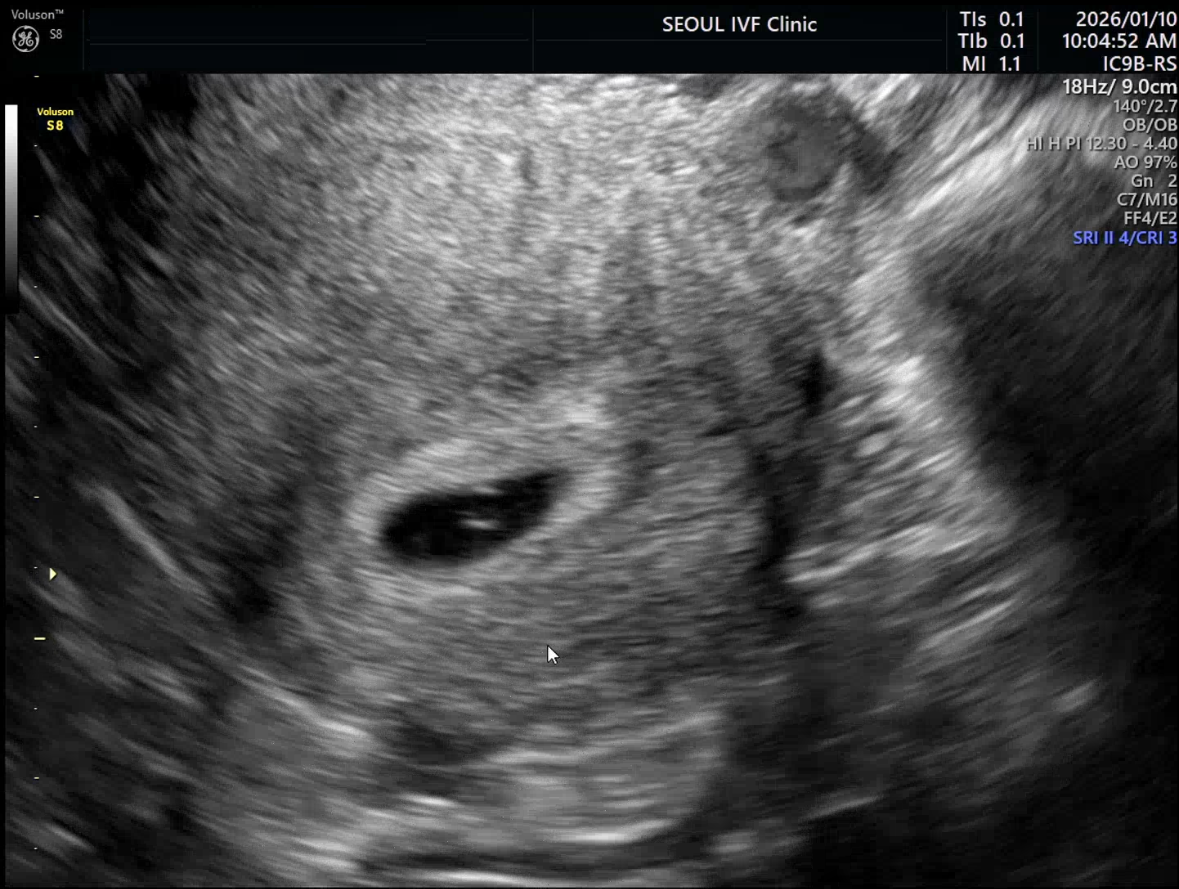

| 가슴 떨리는 임신 이야기를 공유해 주세요. | 시험관 동결 1차 시도에서 임신에 성공하게 되었어요. 예상보다 오랜 시간이 걸리지 않아 더욱 감사한 마음입니다. |

| 서울IVF여성의원의 난임 치료에 대해 말씀해 주실 것이 있나요? | 이유정 원장님의 빠른 판단과 방향 제시 덕분에 흔들리지 않고 치료를 이어갈 수 있었고, 환자를 많이 배려해 주는 곳이라는 점을 느낄 수 있었습니다. |